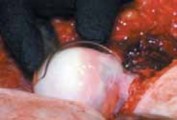

E F

TECH FIG 3 • A. The trochanteric fragment is mobilized anteriorly. The joint capsule is prepared. The insertion of the piriformis tendon onto the trochanter is intact. B. Schematic of the capsulotomy. C. By flexion and external rotation, the leg is placed in the anterior side bag. This maneuver allows anterior dislocation of the hip. D. Overview across the acetabulum after dislocation of the hip. E. Dislocated femoral head. For better visualization, two blunt Hohmann retractors are placed around the femoral neck. The anterior asphericity and the fibrillated cartilage in the area of impingement are visible. F. Intraoperative view of a left acetabulum. A labral ganglion extending into the soft tissues is visible at the anterosuperior acetabular rim, and the anterosuperior acetabular cartilage flap is seen. come posteriorly, creating enough space to visualize the entire acetabulum.

1. The head–neck junction is observed for the presence of a nonspherical extension (

TECH FIG 4

).

32. The femoral head is dislocated anteriorly, making it possible to fully evaluate the femoral head–neck junction as well as the acetabulum.

TECHNIQUES TECH FIG 4 • Inspection of the femoral head in situ. The anterior asphericity can be seen. Dynamic inspection with flexion and internal rotation shows the area of impingement. 1. Acetabular version is assessed and compared with the preoperative radiographs.

2. With a blunt probe, the integrity of the labrum and the articular cartilage is determined, and the quality and quantity of any damage or injury is documented.